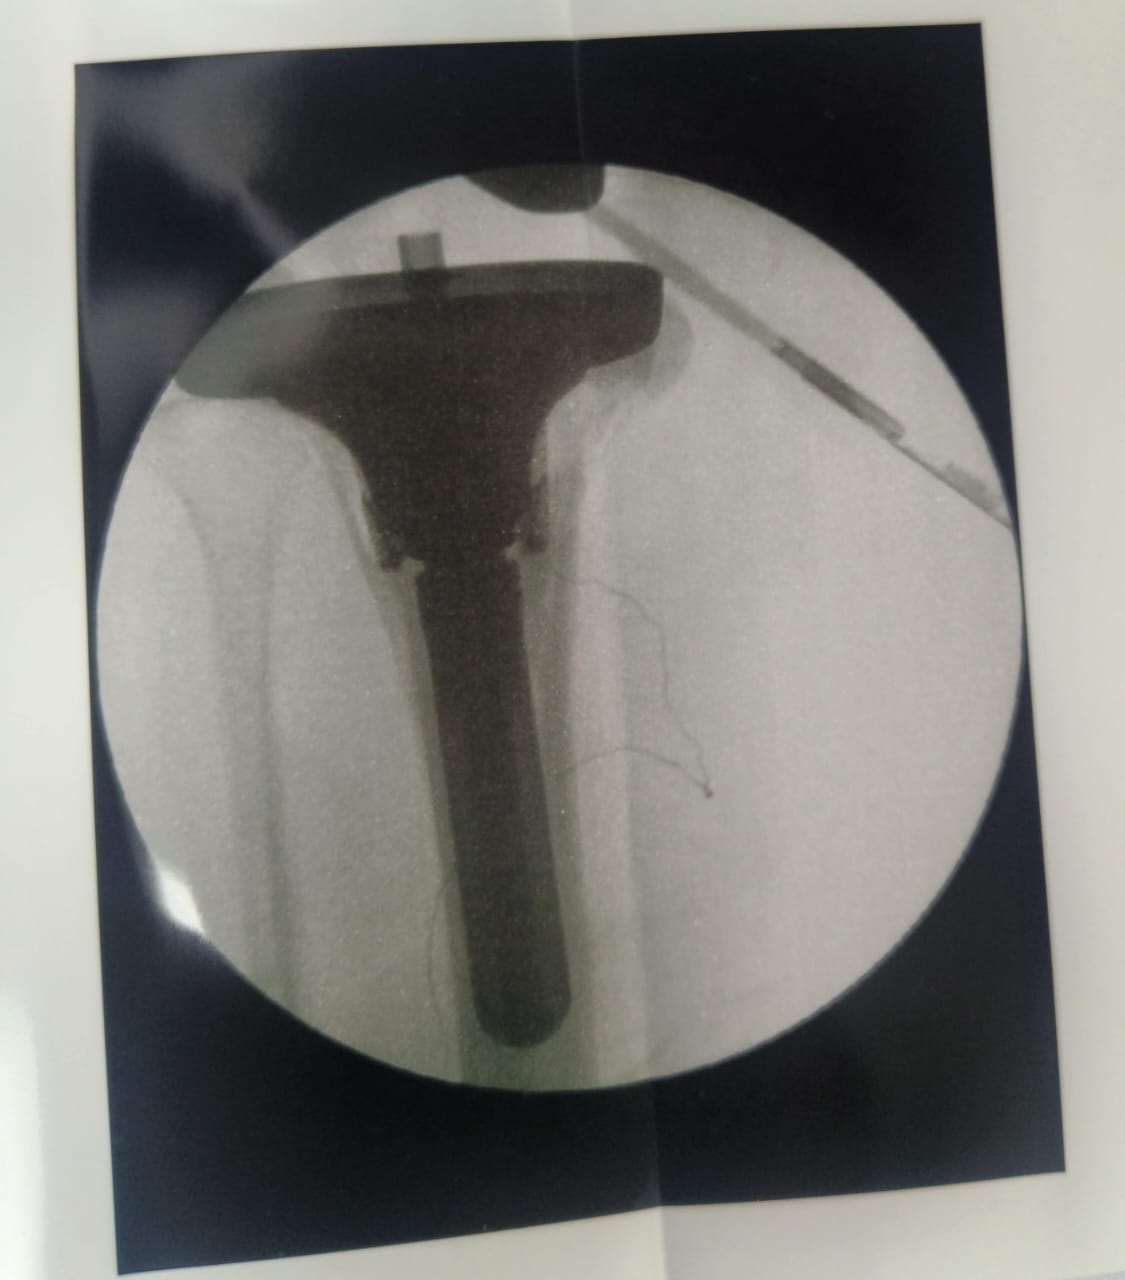

Dr Ajay Randive : IS MS Ortho (Mumbai) MRCSI ( UK) Consultant knee, Hip ,& Spine Surgeon, Dr Ajay Randhive is a eminent Knee, Hip , & Spine Surgeon practicing in to areas Andheri East,Santacruz East. Dr Ajay Randive did his MS Ortho residency from LTMMC, Sion Hospital Mumbai. He did overseas training in UK from 2003 till 2008. He is trained in total Knee Replacement, Hip Replacement, Revision Hip Replacement And Revision Knee Replacement Surgeries. He has worked at The Royal London Hospital. IN London where he worked a clinical fellow in joint Replacement unit. He has carried out more than 5000 Knee Replacement surgeries, 2500 Hip Replacement Surgeries, More Than 500 Revison Knee And Hip Replacement Surgeries 600 Spine surgeries & more than 1500 arthroscopic surgeries (Knee & Shoulder).